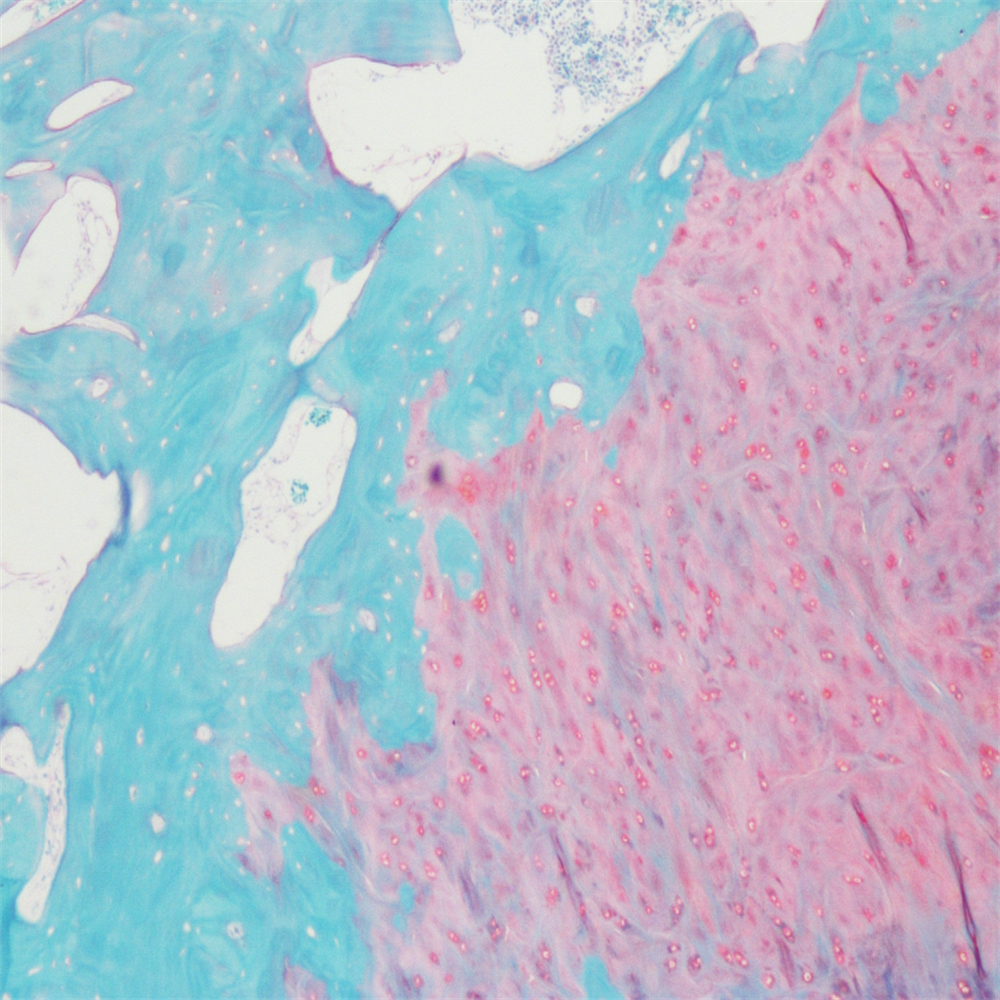

番红固绿染色

番红-固绿染色

番红-固绿染色(软骨)在涉及关节软骨及软骨下骨的形态学研究中,常需联合使用多种染料以显示其组织学结构。其中,起源于上世纪60年代的番红O(safranin O)-固绿(fast green)染色因可以直观反映关节软骨、软骨下骨和骨组织的结构而备受青睐。软骨呈红色,成骨呈绿色。

番红-固绿(软骨)染色法的染色原理在于嗜碱性的软骨和碱性染料番红O结合呈现红色,嗜酸性的骨和酸性染料固绿结合而成绿色或者蓝色,与呈现红色的软骨对比鲜明,从而将软骨组织和骨组织区分开。番红O是一种结合多阴离子的阳离子染料,其显示软骨组织是基于阳离子染料与多糖中阴离子基团(硫酸软骨素或硫酸角质素)结合。番红O着色与阴离子的浓度近似成正比关系,间接反映基质中蛋白多糖的含量和分布。当软骨收到损伤时,软骨中的糖蛋白会释放出来,使基质成分分布不均匀,从而导致番红O淡染或不着色。通过图像分析软件可以对番红O染色的软骨基质进行定量分析。固绿与胶原纤维结合,不宜褪色。

<番红固绿-骨>